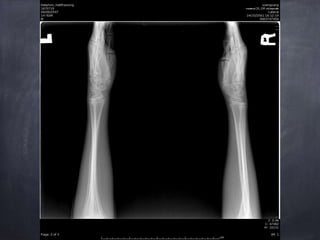

Diagnosis

Epiphyseal plate injury Salter harris type 2 Lt.

distal end redius